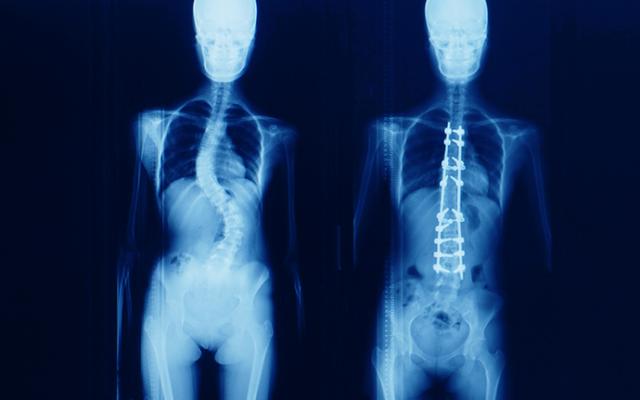

También puede ordenarle unas radiografías de la espalda para mostrar la posición y el tamaño de la curvatura. A la curvatura se le da una medida en grados, denominada ángulo de Cobb. El radiólogo o cirujano pueden comparar radiografías anteriores con las más recientes para determinar si la curvatura está estable o se vuelve más pronunciada.

La técnica más común es la fusión espinal, en la que los huesos afectados de la columna vertebral son enderezados y luego se fusionan (unen) entre sí. La curvatura se corrige mayormente por varillas metálicas y tornillos que se ajustan en la columna vertebral.